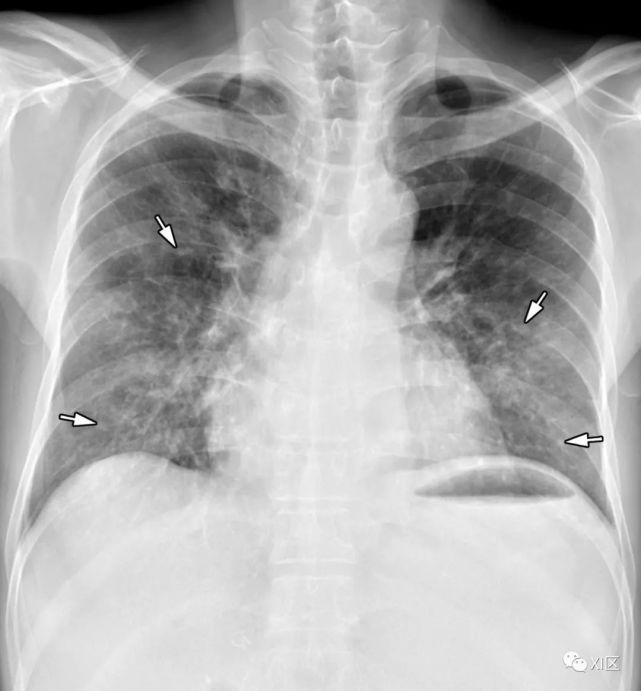

流感肺炎患者的影像学表现为双侧网状结节样阴影区伴或不伴局灶性实变,通常位于下叶。定义不清的斑片状或结节性实变区,迅速融合,表现为弥漫性肺泡损伤或重叠感染,常见于3周内消失继发性细菌性肺炎可发生,尤其是肺炎链球菌感染具有重要的相互作用,可能存在共感染或继发感染。在退热一段时间、白细胞计数增加和放射学异常改变后出现继发性发热时,可怀疑合并细菌感染。小叶实变对细菌性合并感染的诊断尤其有帮助。革兰氏染色、痰培养或支气管肺泡灌洗也是确诊疑似合并感染的有效方法。

图20 38岁孕妇因甲型流感病毒引致的肺炎,怀孕29周零5天,出现咳嗽及呼吸困难。(上) 最初的胸片显示两肺广泛的斑片状实变(箭),空气支气管征(箭头),特别是在中下肺区。患者进行紧急剖宫产后,对急性呼吸窘迫综合征进行了插管和体外膜充氧。(中) 3周后胸片显示不规则实变强度降低(箭)。(下)在同一天的轴位CT图像显示沿支气管血管束的不规则实变(箭头),弥漫性GGO伴肺小叶间隔增厚(箭头)。对患者进行逆转录聚合酶链反应(RT-PCR)痰、血培养及支气管肺泡灌洗,寻找混合感染的证据。然而,没有证据表明有混合感染。

Koo H J , Lim S , Choe J , et al. Radiographic and CT Features of Viral Pneumonia[J]. Radiographics, 2018, 38(3):719-739.